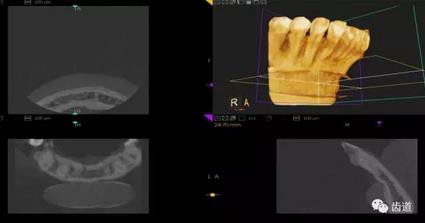

三)種植修復(fù)

CBCT在牙種植修復(fù)中的應(yīng)用。種植前利用CBCT對患者的牙床進行檢查,可精準(zhǔn)判斷牙槽骨的寬度、厚度及高度、骨的密度、重要的顏面神經(jīng)、血管和鼻竇位置等。臨床醫(yī)生不僅可以在計算機直觀的看到牙槽骨的立體影像,還可以切換不同的視角來觀察硬組織之間的位置關(guān)系,在手術(shù)方案中避開危險區(qū)域,保證手術(shù)的安全性。臨床醫(yī)生還可以利用CT數(shù)據(jù)進行數(shù)字模型重建,配合軟件預(yù)先做好手術(shù)模板,使種植手術(shù)更安全快捷,避免在種植手術(shù)過程中不慎破壞神經(jīng)、鼻竇等解剖結(jié)構(gòu),導(dǎo)致顏面神經(jīng)麻痹、鼻竇炎等并發(fā)癥的發(fā)生。

1、下頜骨種植牙前測量準(zhǔn)備影像

2、上頜骨種植牙前準(zhǔn)備影像

3、下頜骨種植牙術(shù)后